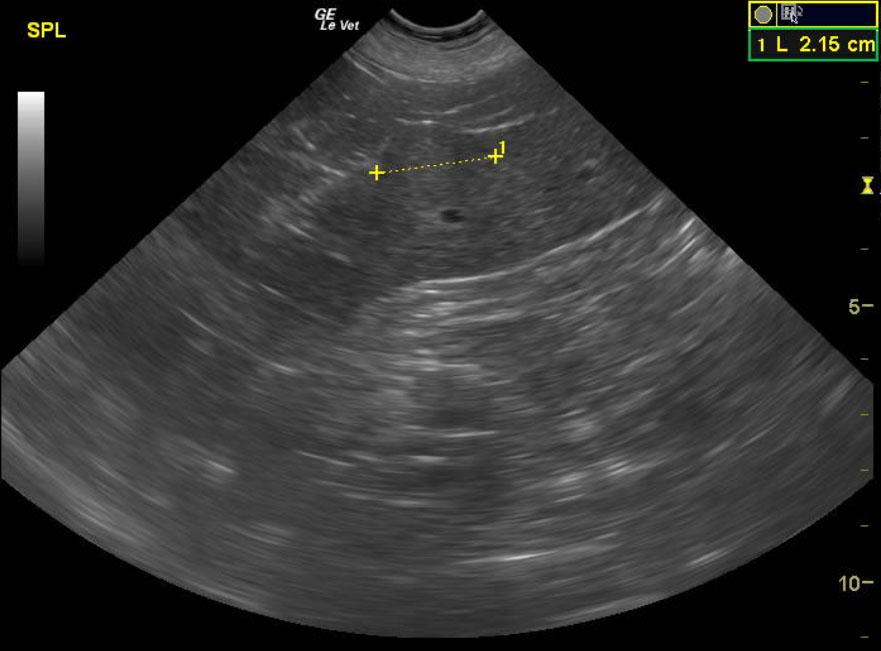

An 11 year old, MN, Rhodesian Ridgeback dog was presented for nonspecific symptoms (ADR). Abdominal mass was palpated. The dog had a subnormal temp (98.8) and pale mucus membranes. Altered CBC/Chem/UA values included leukocytosis, mild azotemia, and mild hypoglobulinemia. Radiographs demonstrated a mass effect in the right abdomen.